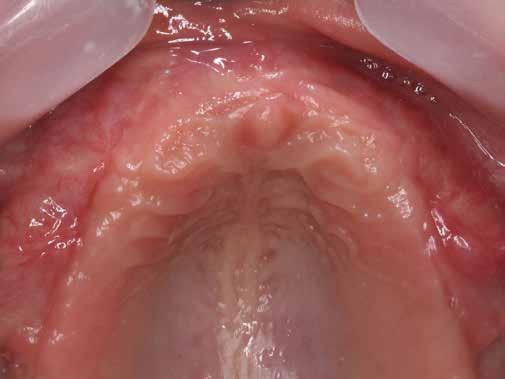

Esetismertetés

Az 50 éves nőpáciens az alsó és felső állcsont területén egyaránt panaszt (fájdalom, ráharapási érzékenység) okozó, harmadfokban mozgatható fogak miatt jelentkezett rendelőnkben. Az általános anamnézisben említést érdemlő betegség, műtét nem szerepelt. Az elvégzett klinikai és radiológiai vizsgálatok (1–2. ábra) alapján fogai reménytelen parodontális státusúnak bizonyultak, hosszú távon sem megtartásuk, sem protetikai célú felhasználásuk nem volt lehetséges. A parodontális prognózis a fogak eltávolításának abszolút indikációját jelentette. Ezáltal mindkét állcsontban teljes foghiány kialakulásával kellett számolnunk. A protetikai szemléletű, „visszafelé” tervezés elveit követtük a hosszú távú funkcionális, esztétikai siker és szöveti stabilitás elérése érdekében: mindkét állcsontban overdenture típusú fogpótlás készítése mellett döntöttünk. A megfelelő implant-protetikai rehabilitáció alapja az implantátumok megfelelő pozicionálása. A korábbi parodontális kórfolyamat következtében a processus alveolarisokat érintő eredendő csontdeficittel kellett számolnunk, amelyet tovább súlyosbíthatott volna a hagyományos extrakciós technikát követő involúciós atrófia. Ezért a páciens kivizsgálása és megfelelő előkészítése után a fog eltávolításával egy időben PRF

27 VI. ÉVFOLYAM – 2023. 4. SZÁM

Sticky Tooth segítségével kivitelezett alveolus prezerváció mellett döntöttünk, a megfelelő csontos és mukogingivális gyógyulás minőségi és mennyiségi elősegítése érdekében. A PRF készítmény mennyiségét, minőségét, kezelhetőségét és hatékonyságát jelentősen befolyásolják a páciens laborértékei, ezért kezelési protokollunk szerint a műtétet megelőzően minden esetben laborvizsgálatot végzünk (hemoglobin: 134 g/liter, hematokrit: 0,43, fehérvérsejt: 6,6 G/liter, CRP: 13,60 mg/liter, vércukor: 6,2 mmol/liter, összkoleszterin: 7,00 mmol/liter, triglicerid: 1,08 mmol/liter, HDL koleszterin 2,57 mmol/liter, LDL koleszterin 1,12 mmol/liter), D3 vitamin: 117,5 nmol/liter).

A fogak eltávolítása és az alveoláris csont megőrzésének és regenerációjának segítése céljából elvégzett augmentáció altatásban történt. Óvatos, atraumatikus extrakciót követően eltávolítottuk a parodontális és periapikális gyulladásos folyamatok eredményeként jelen lévő sarjszövetet. A bukkális csontfal hiánya és a tervezett vertikális augmentáció miatt indokolt membrántechnika megfelelő kivitelezése céljából a felső állcsonton mukoperioszteális lebenyt képeztünk (3–4. ábra). Az alveolus prezervációt Sticky Tooth, PRF és titánerősítésű teflon (PTFE-Ti) membránok segítségével végeztük el, a J. Choukroun által megadott vérvételi és centrifugálási protokoll (28) elveinek betartásával: kizárólag Process for PRF Duo Quattro System eszközöket, centrifugát, vérvételi egységet és csöveket, a membránok előállításához PRF Boxot használtunk. Az A-PRF és S-PRF csöveket a PomPac eljárásnak megfelelően 4 Celsius-fokra előhűtöttük. Az eltávolított fogak makroszkópos tisztítását és darabolását nagy fordulattal (300 000 RPM) fogászati turbinába helyezett gyémántfúróval végeztük, majd Tooth Transformer™ berendezéssel, annak gyári reagens rendszerével kezelt őrleményt nyertünk. A Sticky Tooth készítmény előállítása a PRF készítmény és az őrlemény